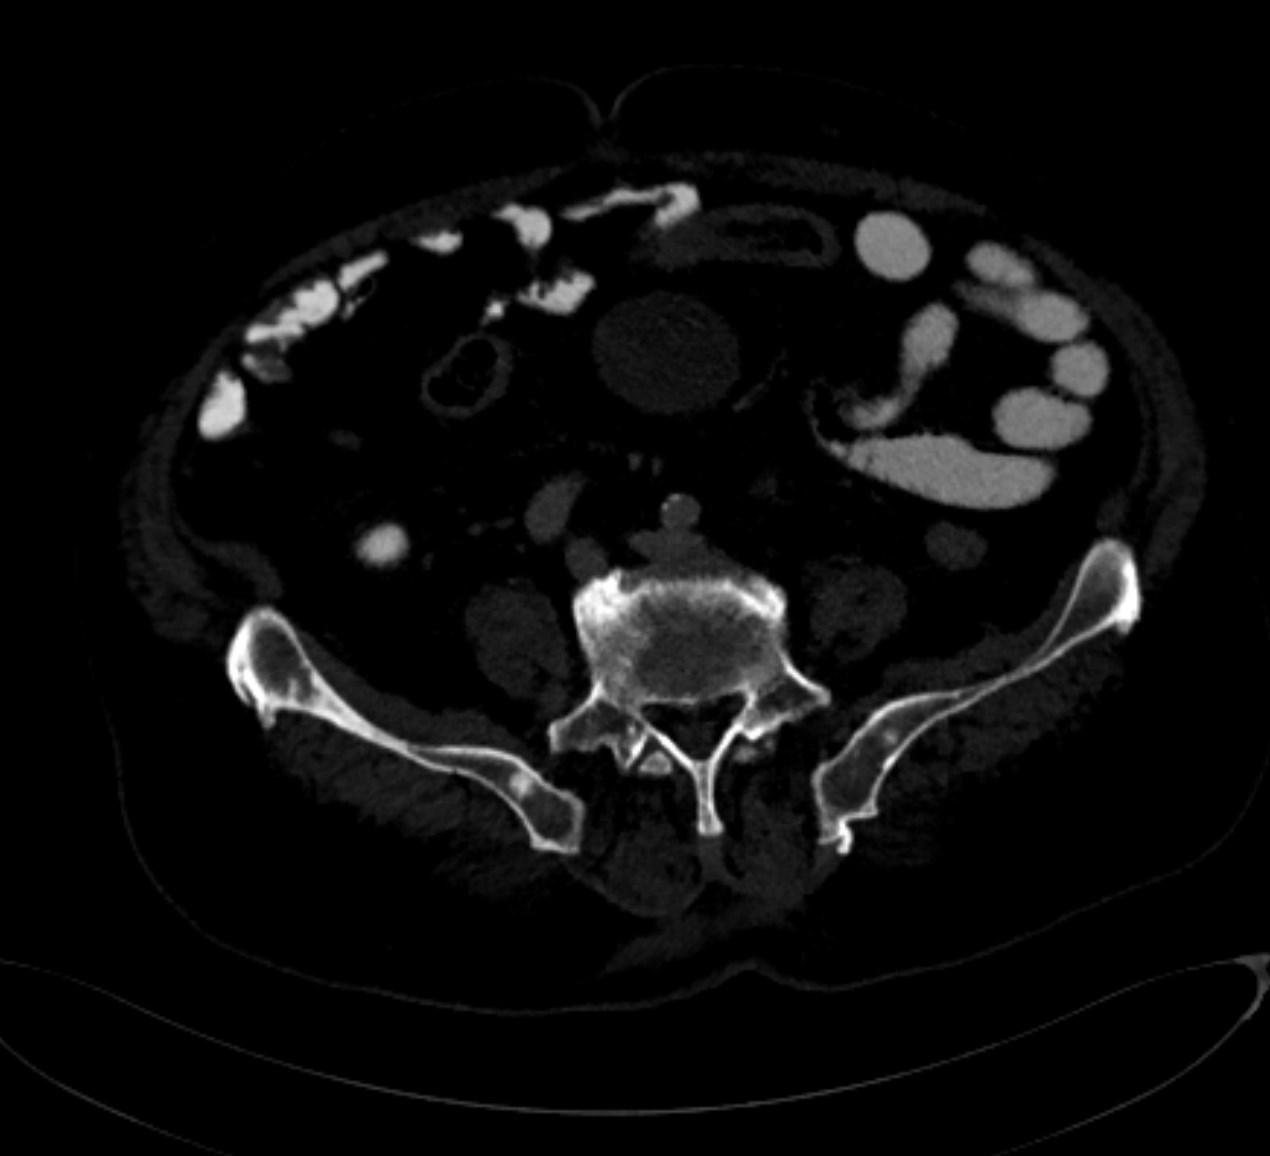

*73-year-old male present with bone pain.

What is the most likely diagnosis?

Sclerotic bone metastases (prostate carcinoma)

CT images revealed sclerotic bone metastases.